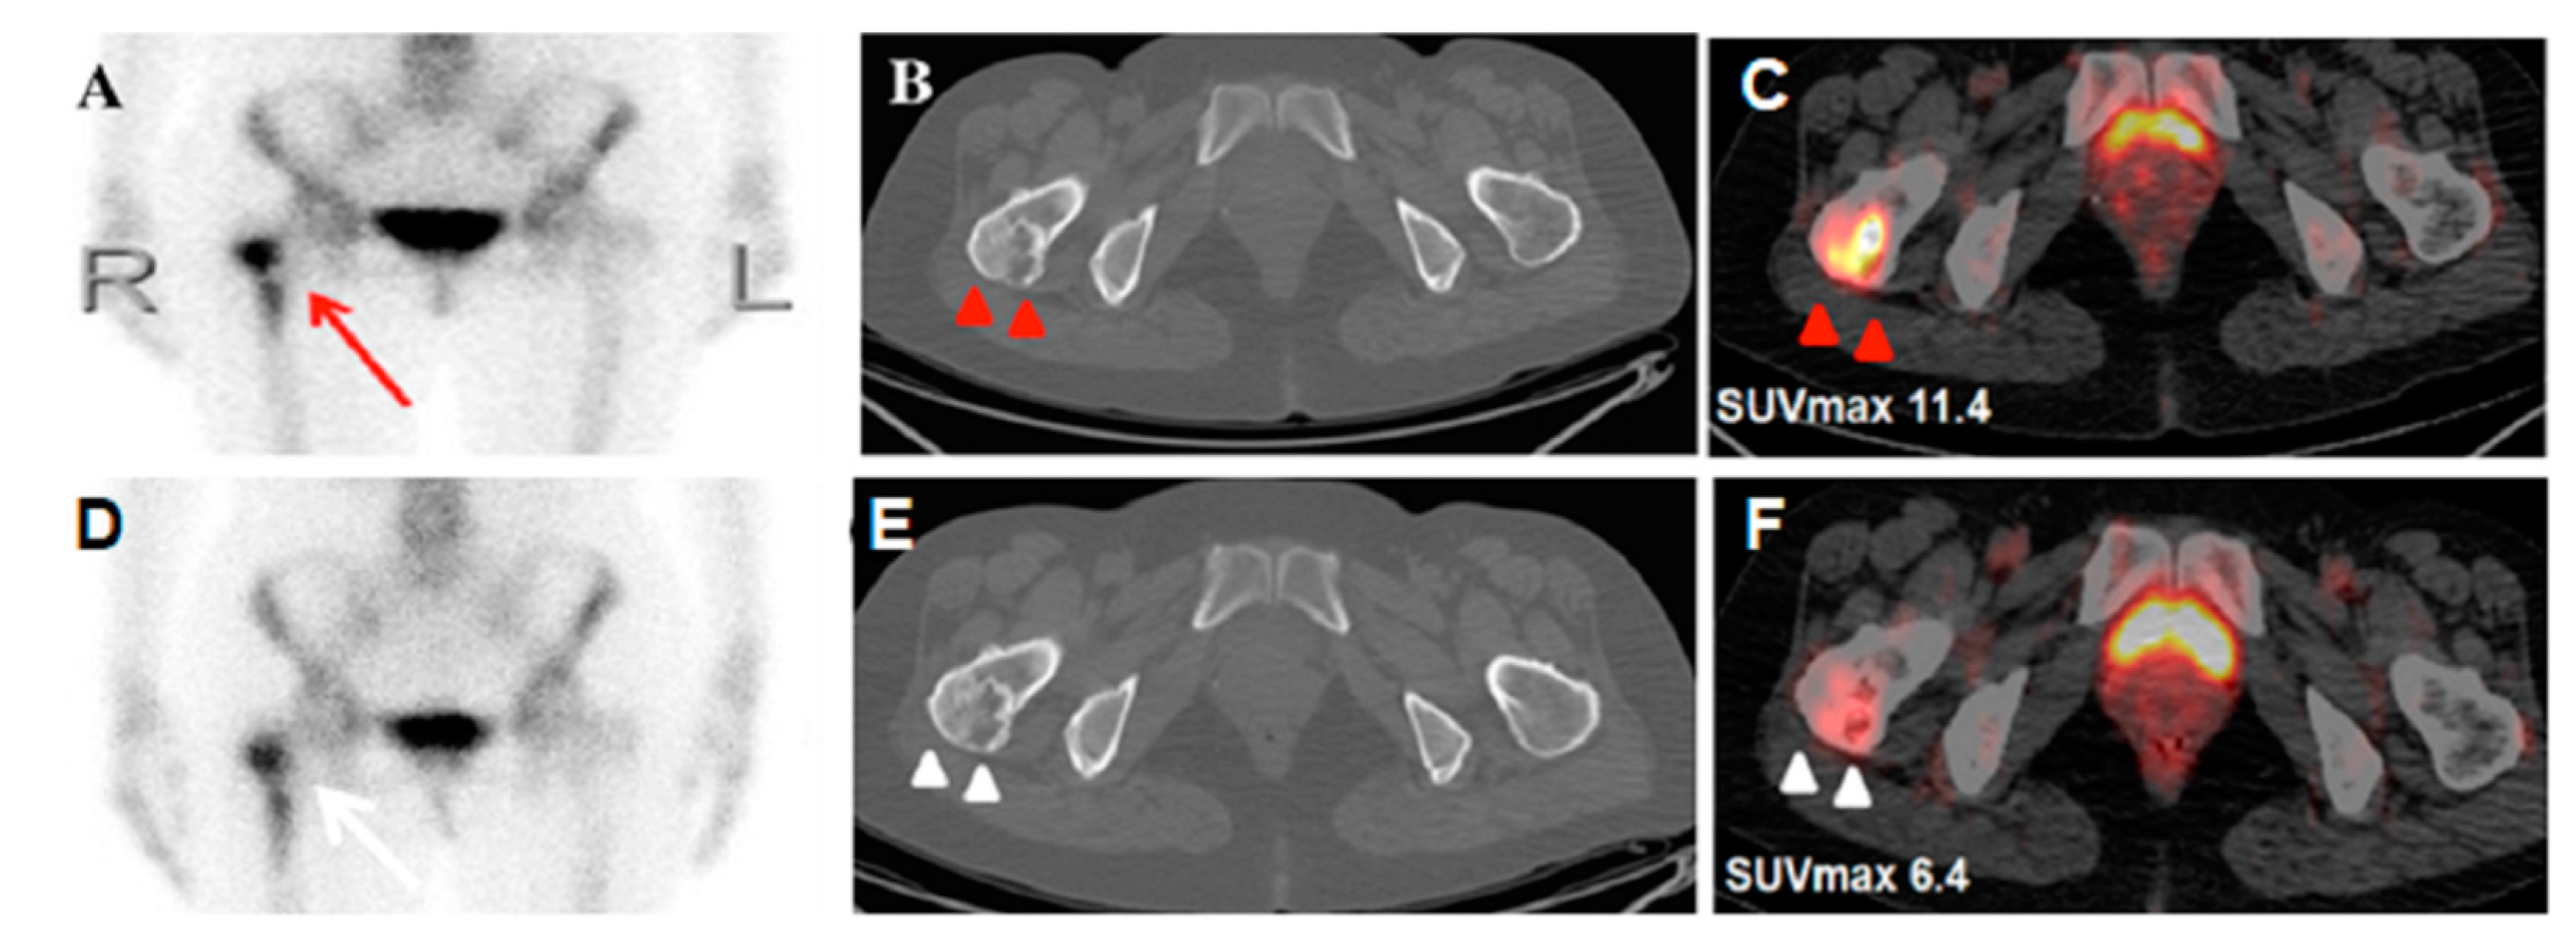

Monostotic Fibrous Dysplasia Mimicking Metastasis in the Femoral Neck on Bone Scintigraphy and 18F-FDG PET/CT